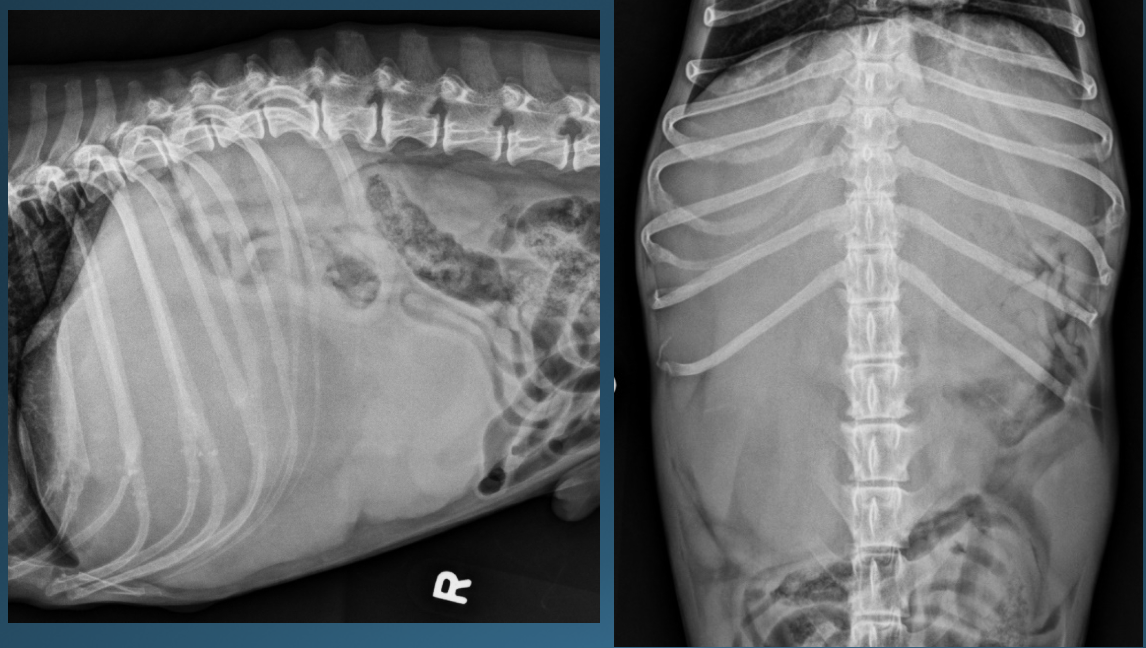

What is shown in these images?

*generalized hepatomegaly:

-extends past costal arch

-gastric axis no longer parallel with ribs; pylorus pushed caudal